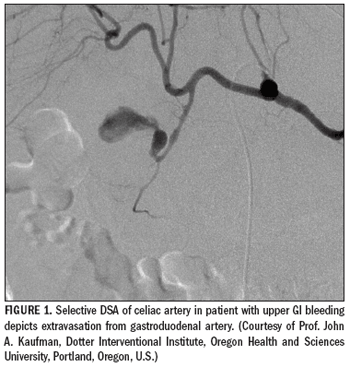

Gastrointestinal bleeding is a frequent cause ofhospital admissions. Patients present withmelena, hematemesis, hematochezia, and/orshock. GI hemorrhage usually stops spontaneouslyor responds to conservative management.